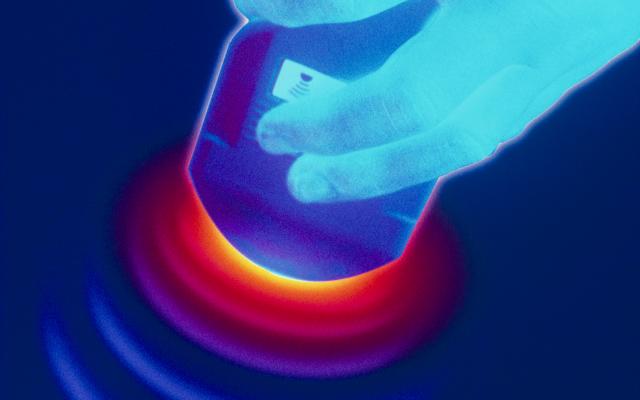

Een 9-jarige jongen kwam op de afdeling Spoedeisende Hulp vanwege een pijnlijke zwelling in de rechter lies. Hij had de dag tevoren pijn gekregen rechts in de onderbuik, waarbij hij de zwelling had opgemerkt. De pijn verdween met pijnstillers na een bezoek aan de huisarts. ’s Nachts nam de pijn weer toe en gaf patiënt veel over. De huisarts stuurde hem door. Wij vonden een pijnlijke zwelling in de rechter lies, met daarnaast een leeg scrotum aan de rechter zijde. Op patiënts zogenaamde ‘ballenkaart’ was in het verleden wel indaling van de testis gedocumenteerd. Bij echografie werd een getordeerde…